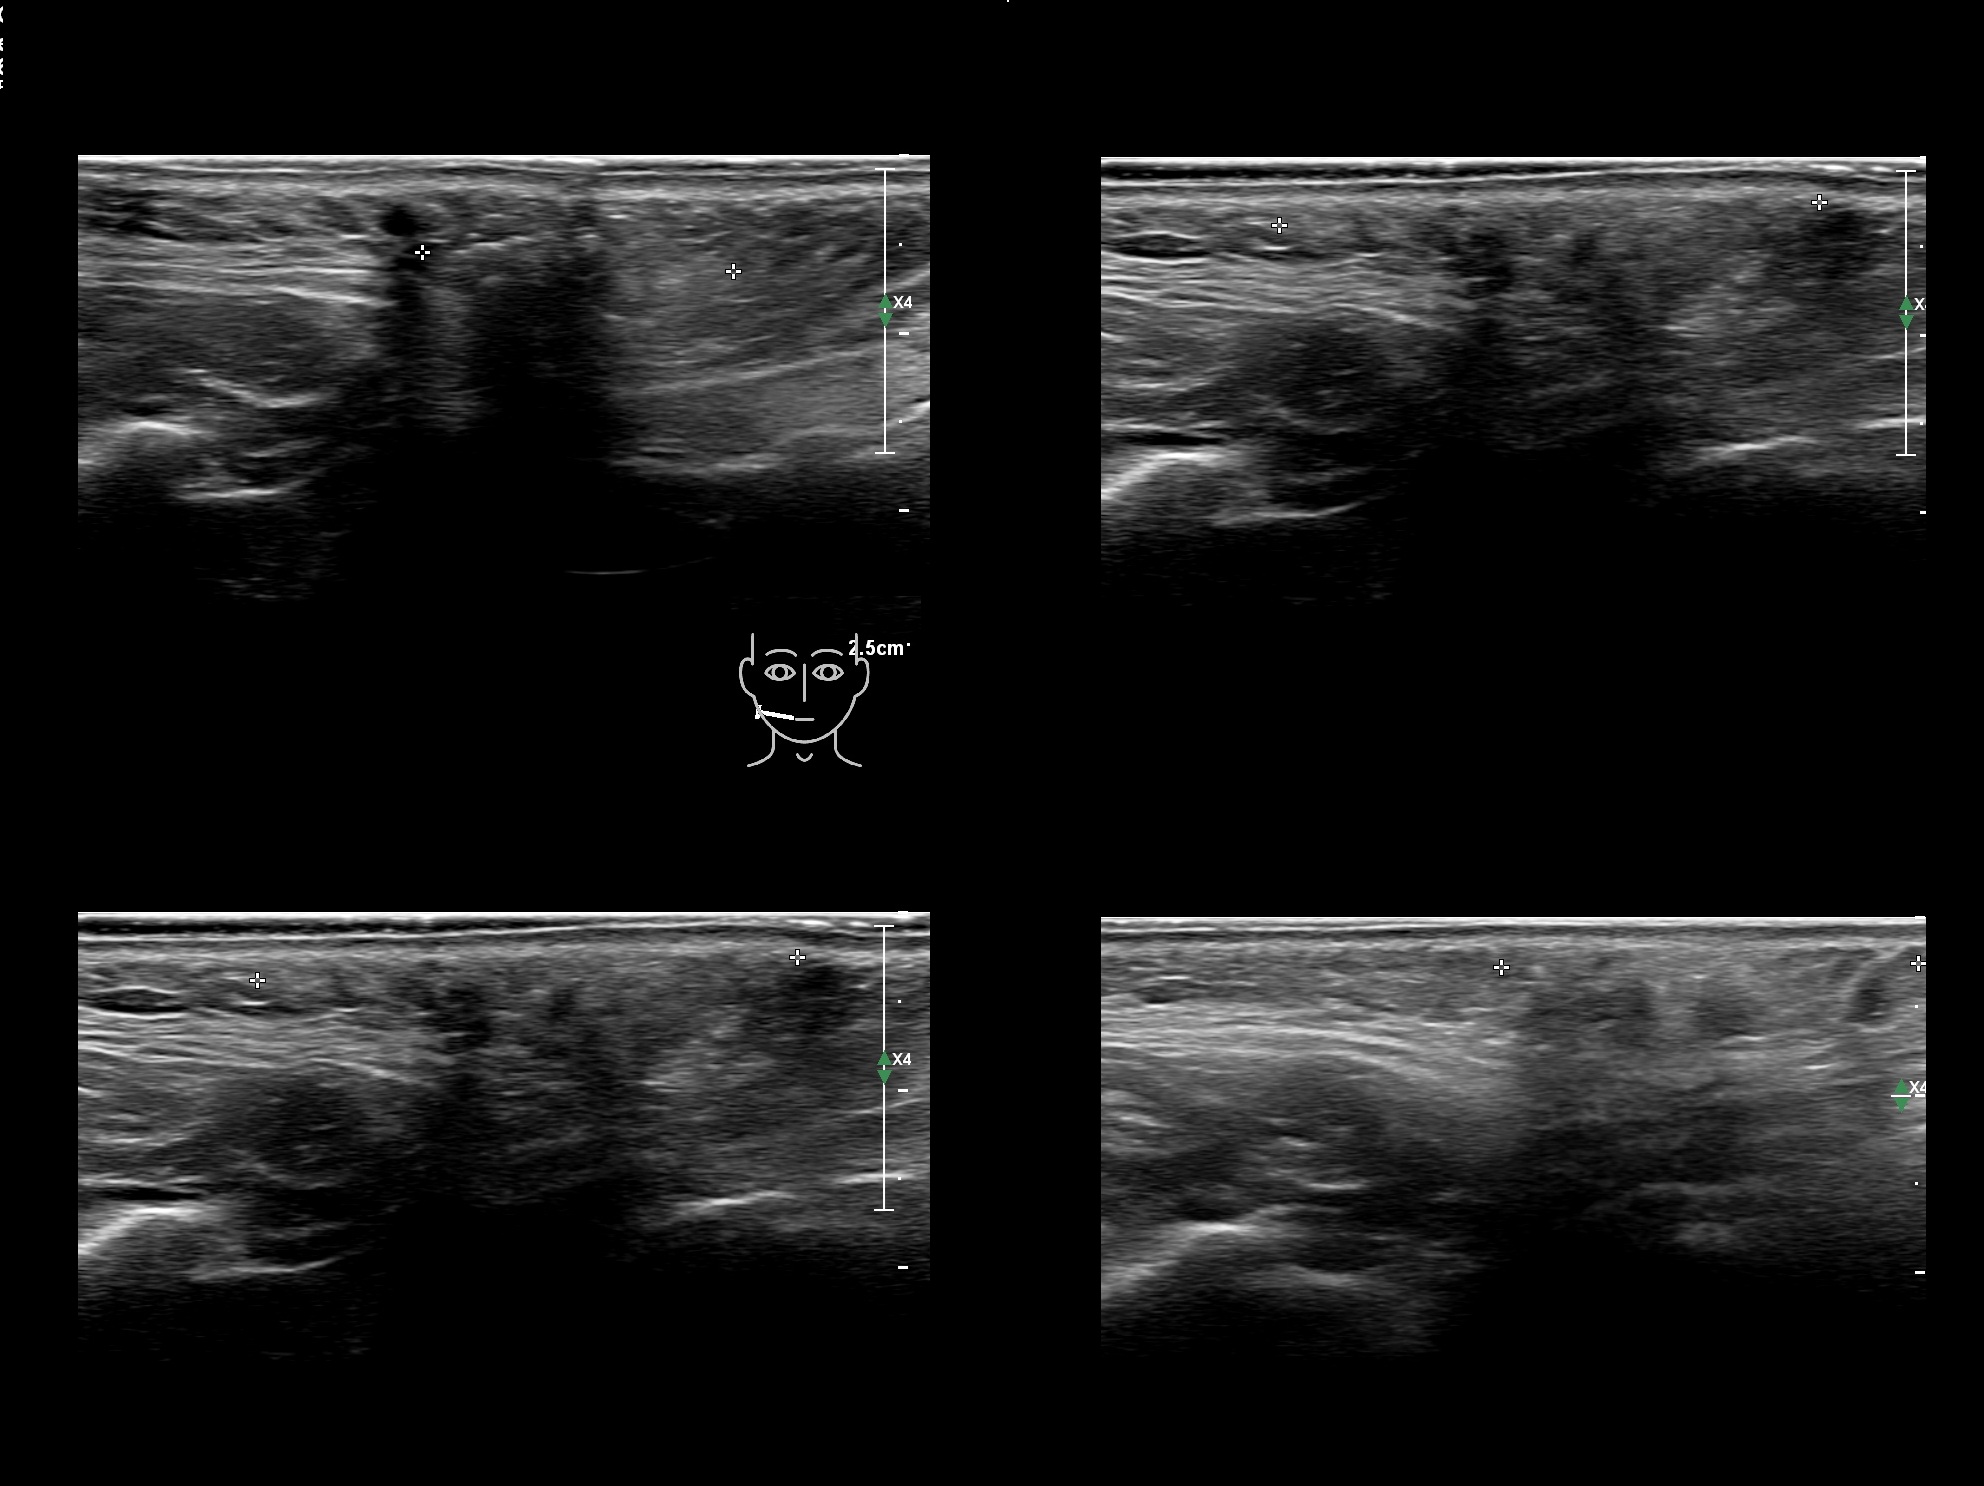

Filler library